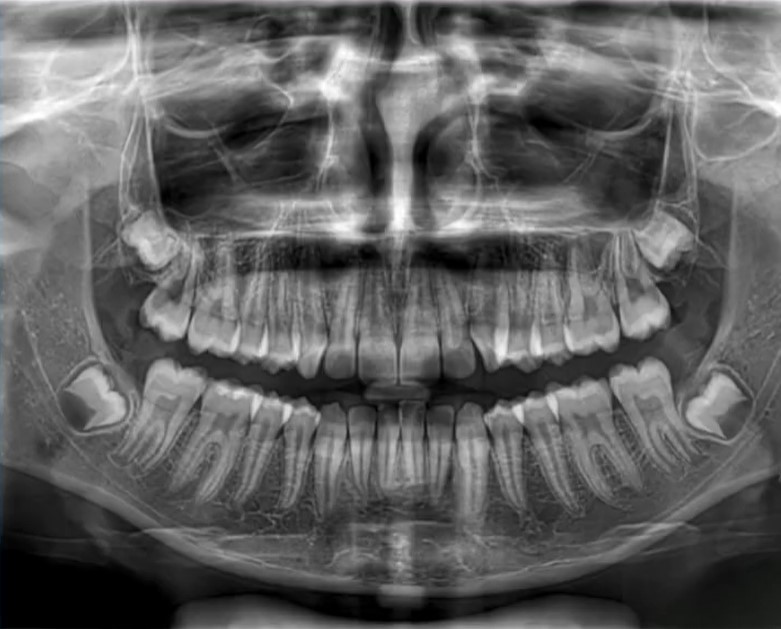

2) Radiografie: panoramica e teleradiografia latero-laterale

Ortopantomografia per una visione generale (in questo caso erano presenti anche i 4 denti del giudizio, senza necessità di estrazione per creare spazio).

Teleradiografia latero-laterale + cefalometria, utile per misurare inclinazioni e rapporti scheletrici: ad esempio, qui gli incisivi inferiori risultavano un po’ pro-inclinati (troppo “in fuori”).